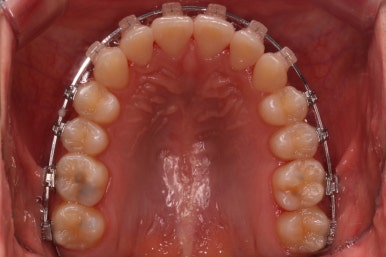

부산부정교합 키다리아저씨치과에서 장치를 처음 부착한 모습입니다.

많이 삐뚤어진 부위는 철사가 굽이굽이 지나가는 것을 볼 수 있습니다. 이 철사가 점점 직선으로 가지런해지면서 치아가 바르게 가지런해집니다.

부산부정교합 키다리아저씨치과에서 처음 장치를 부착한 모습입니다.

지그재그 방향으로 치열이 변해가는 중입니다.

이렇게 덧니가 가지런해지는데 1년도 채 안걸렸습니다.

마찬가지로 지그재그 방향으로 치열이 변해가는 모습입니다.

윗니들만 보면 이런 모습으로 변해가고 있습니다.